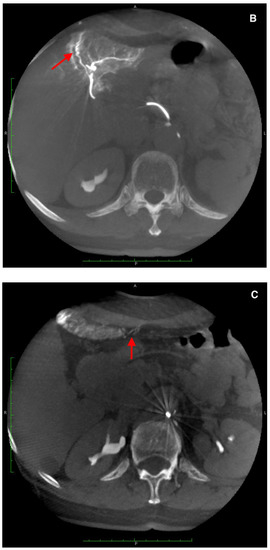

There were two leaks into the gallbladder wall after SIRT administration. Both patients had no signs of cholecystitis or a bilirubin level elevation (Figure 6 and Figure 7). No leaks were noticed in the group of five requalified patients.

Figure 7.

A computed tomography scan depicting asymptomatic cholecystitis (arrows) after the 90Y leak. The patient did not require surgery and was treated conservatively.